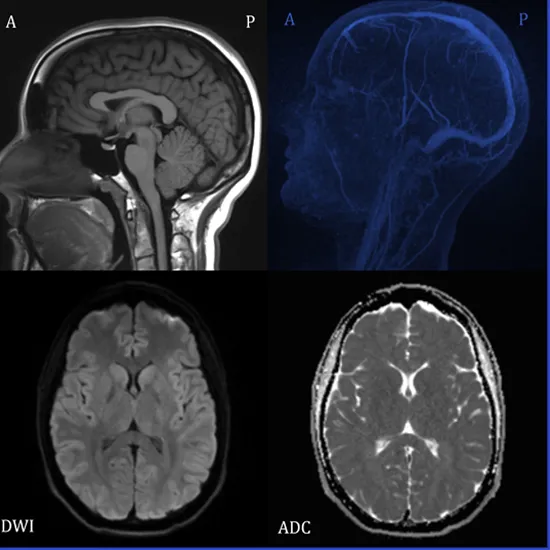

MRI is the best imaging modality of choice for epilepsy investigation, especially with 3Tesla MRI. The test is done to detect the areas of scar tissue, brain lesions, blood vessels abnormalities or changes in normal brain tissue that could cause seizure.

MRI brain epilepsy protocol is a group MRI sequences or a combination of studies that put together to improve sensitivity and specificity in detecting the underlying causes of seizures.

MRI brain Epilepsy protocol involves following parameters and planning-

• Sequence:  Evaluation of brain is done in axial and coronal position or isotropic acquisition

To evaluate the brain anatomy and morphology

Measures cortical thickness and checks the grey-white matter differentiation

Visualize unusual location of grey matter as in grey matter heterotopias

Sequence: Study should be done in axial and angled coronal scans

To evaluate the cortical or sub cortical hyperintensities where deep grey matter is also involved

Axial/ Flair/coronal oblique 2mm/ TSE/ Flair axial oblique hippocampus/ flair sagittal hippocampus 2mm SFOV

Evaluate the presence of product of hemoglobin breakdown as in post traumatic bleed and cavenomas.

DWI/ ADC